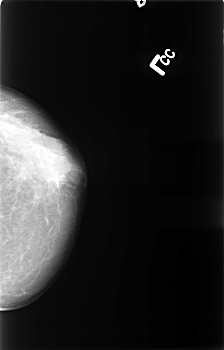

B_3389_1.RIGHT_MLO

DATE_OF_STUDY 17 2 1993

PATIENT_AGE 68

DENSITY 3

FILE: B_3389_1.RIGHT_MLO.OVERLAY

TOTAL_ABNORMALITIES 1

ABNORMALITY 1

LESION_TYPE CALCIFICATION TYPE PLEOMORPHIC DISTRIBUTION CLUSTERED

ASSESSMENT 4

SUBTLETY 4

PATHOLOGY MALIGNANT